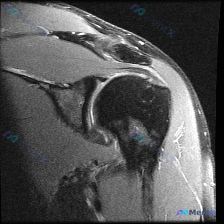

今天碰到一个有意思的病例:临床主诉怀疑肩部软组织有积液,但给到的只有一张肩部MRI T2加权轴位图像,我们一起来整理一下分析思路。 病例核心信息 临床怀疑「肩部软组织积液」,提供单张肩部MRI T2序列轴位图像 - 图像质量:信噪比较低,有一定伪影,主要解剖结构可辨认 - 影像读片结果: 1. 骨骼...